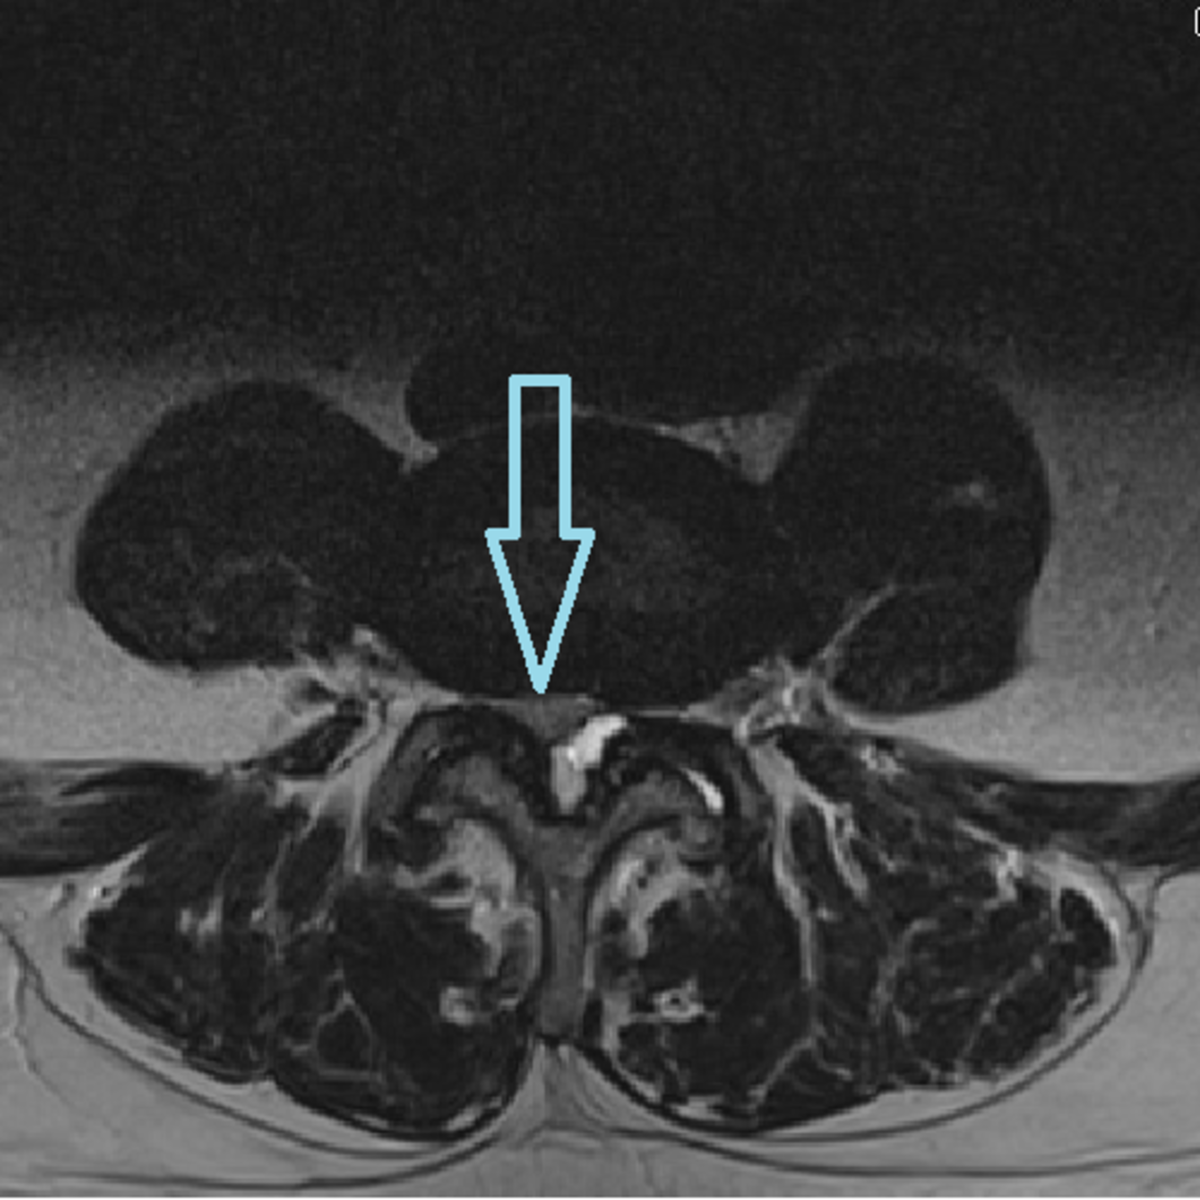

Zur Therapie stehen unsere modernen Großgeräte wie Computertomographen und Durchleuchtungsgeräte (Zwei-Ebenen-Angiographie) zur Verfügung, die schonendes und präzises Arbeiten im Millimeterbereich gewährleisten, was der Sicherheit und der Verbesserung der klinischen Ergebnisse für unsere PatientInnen dient.

- Minimalinvasive CT-gesteuerte Schmerztherapien

- Periradikuläre Therapie